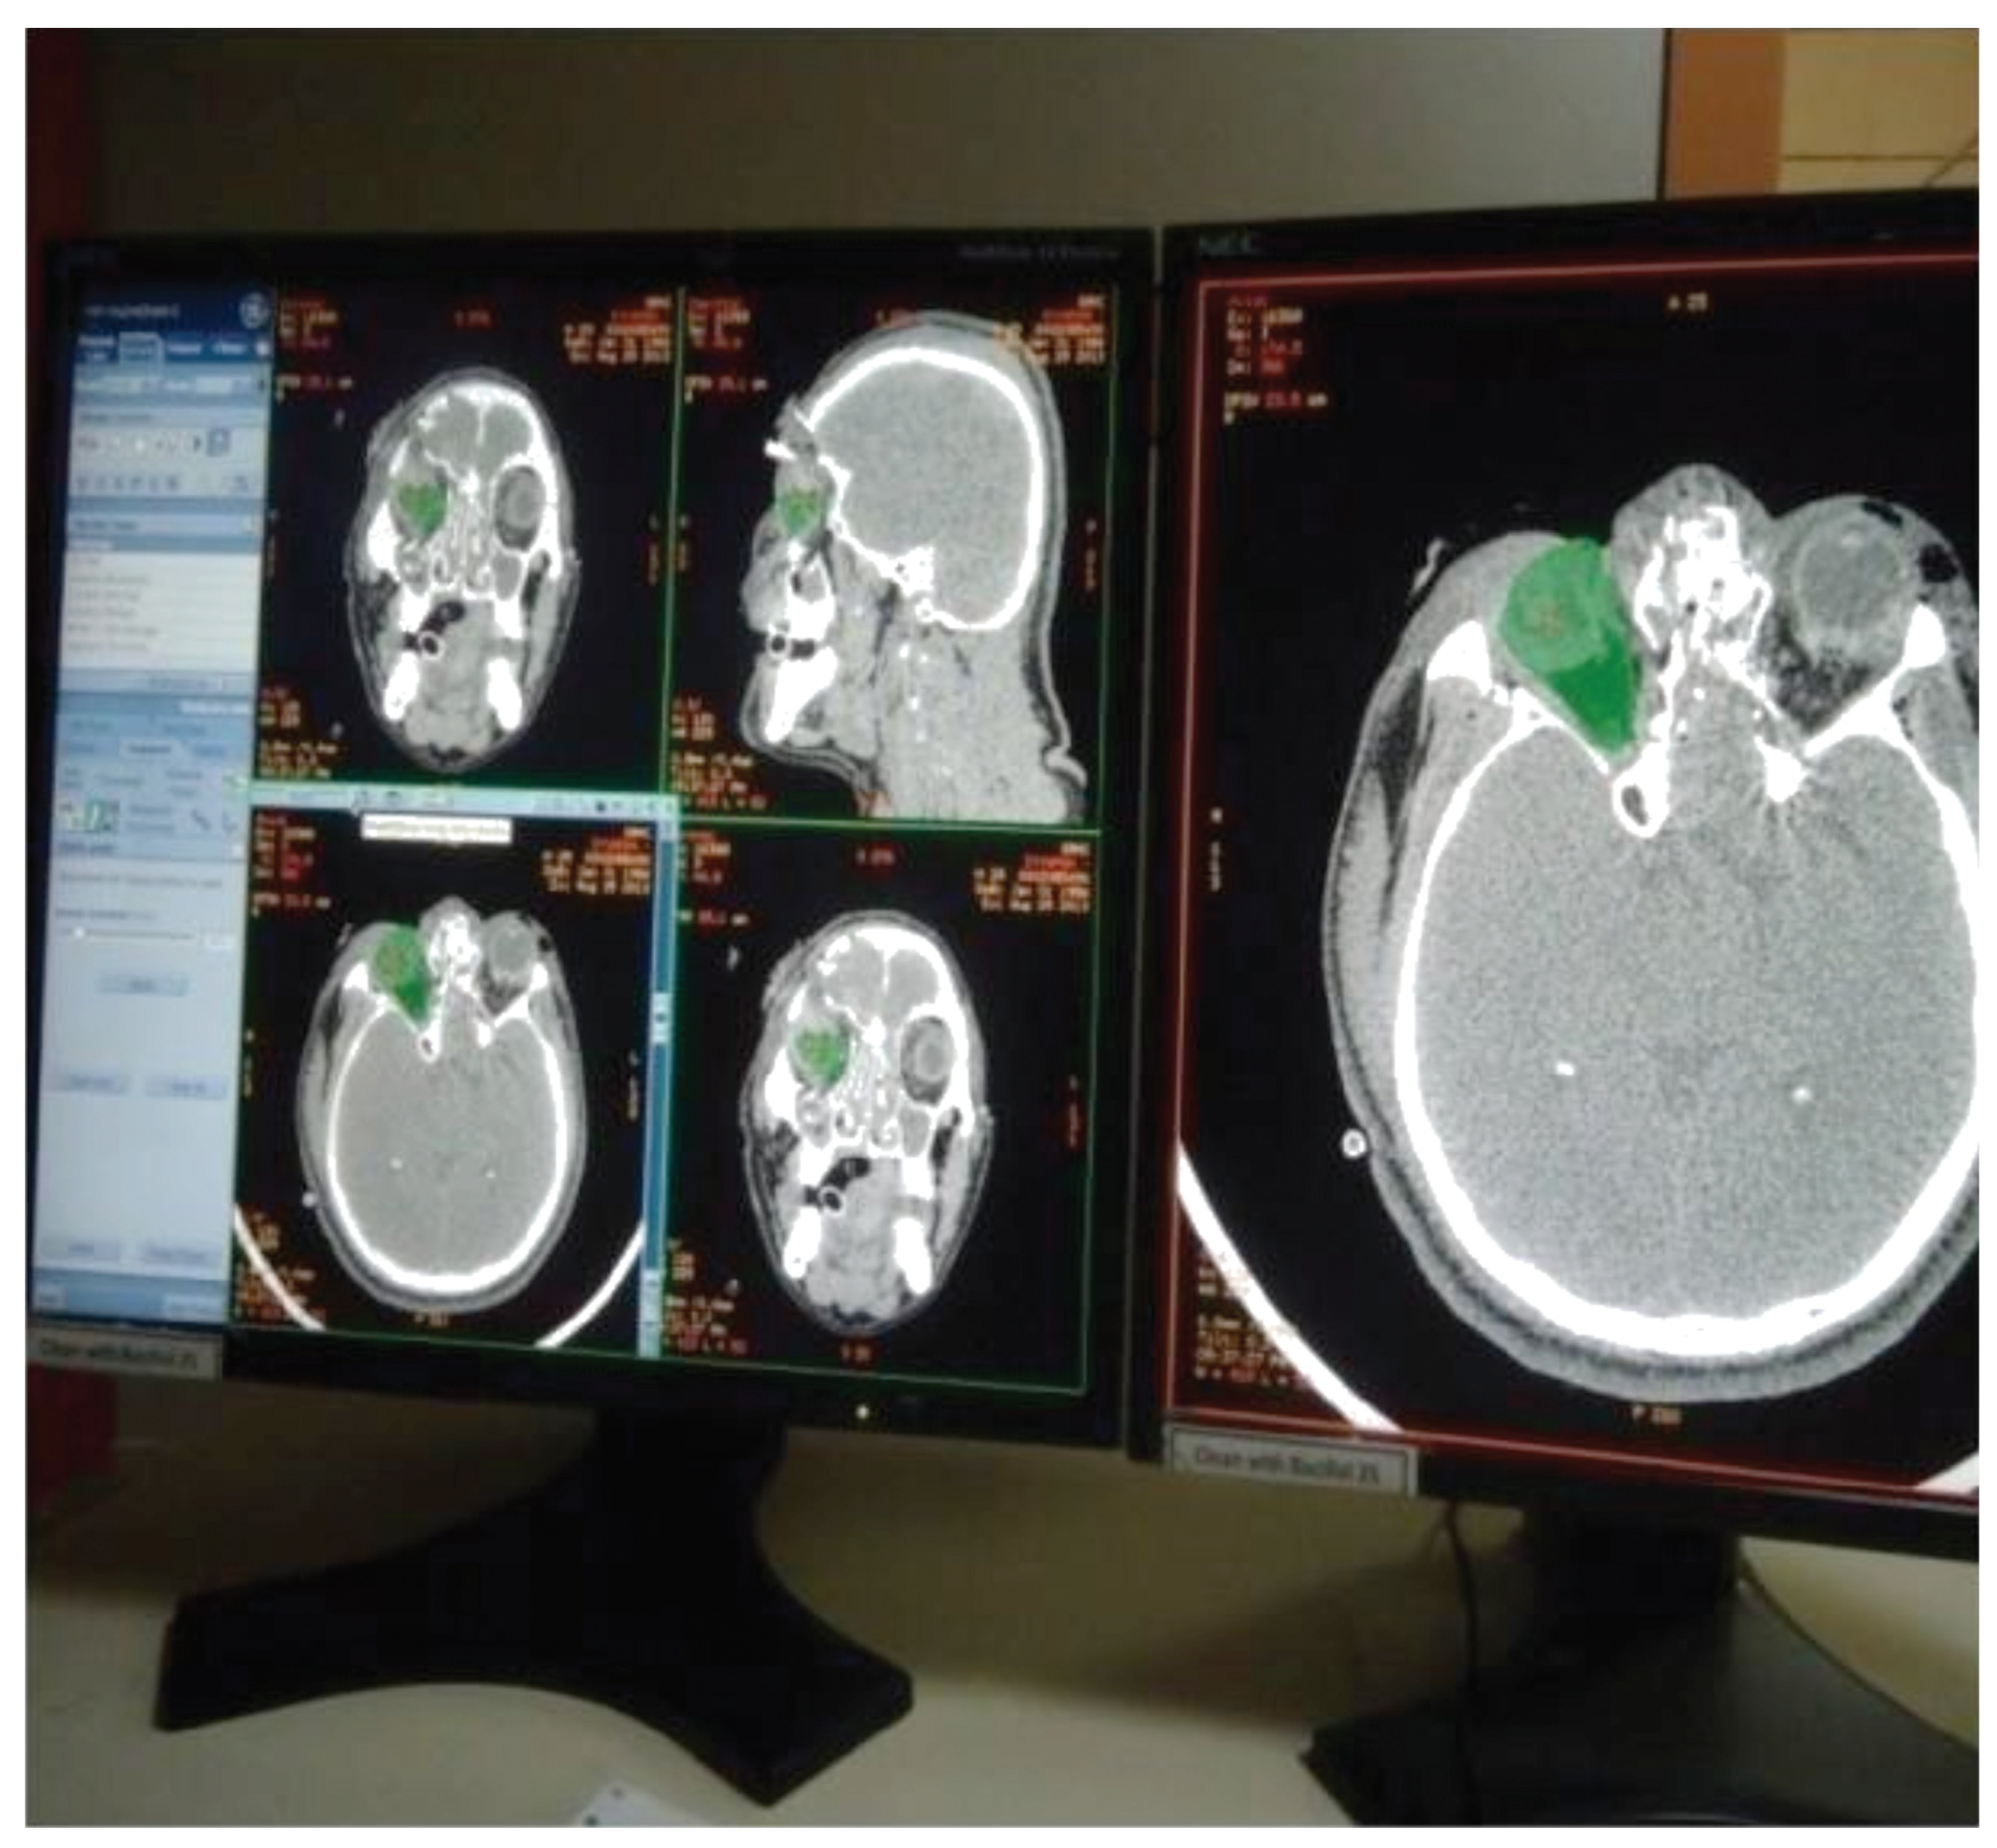

Figure 3.

Images showing output of orbital volume.

All patients were kept on standard postoperative regimen [9,10] of antibiotics and a repeat CTwas done after 2 weeks. The orbital volume was calculated virtually using advanced imaging software (volumetric computed tomography (CT-VCT) [11] 64 slice XT console, 120 kV, 250 mA, and slice thickness with appreciation of 2 mm). The volume of the injured and the uninjured orbits were calculated and tabulated. Orbital volumes were assessed in postoperative CT scans and the change in volume was calculated and the restoration of orbital volume in both groups were calculated and tabulated.

Figure 4.

Figure 5.

Using CT-VCT 64 slice XT console, preand postoperative CT [12] scans were done for the patients with 120 kV, 250 mA, and slice thickness with appreciation of 2 mm. Retro reconstruction was done at 0.625 mm in a bone window of window width 2,000 and window length 350: soft-tissue window of window width 300 to 350 and window length 100 in an advance workstation ADW 4.4. The anterior border of the orbital floor was determined using first CT slice and the posterior border is the apex of orbital cavity. Orbital volume [13] is measured in axial, sagittal, and coronal sections (Figure 1 and Figure 2) by selecting mapping tool provided with the software of computer program, and orbital volume within the bony borders is mapped in every slice to calculate the orbital volume automatically displayed on the monitor (Figure 3, Figure 4 and Figure 5) after the end of mapping.